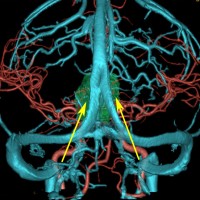

小さな松果体奇形腫です。

OTAでこの奇形腫を見ようとする場合に,テントを静脈洞交会の低い位置まで切断しなければ,直静脈洞の横から松果体部をみることはできません。また,黄色の矢印の方向に視野が入るので,まず最初に邪魔になるのは小脳上極です。上小脳層を左右ともに十分剥離すると,小脳が可動化して,その向こうに,precentral cerebellar veinが見えます。このveinをガレン大静脈への流入部から小脳前面に沿って剥離していくと,小脳上極がさらに可動化して松果体への視野が開ます。

松果体腫瘍の手術では,中脳背面を見る必要があります。特に上丘とそれに連続する後交連 posterior commissureを十分に観察するために周囲組織の剥離を行います。具体的には迂回槽と下丘の周囲のクモ膜組織を剥離します。対側中脳と迂回槽を見る時に妨げになるのが,緑の矢印で示した直静脈洞です。テントが長く切断してあって直静脈洞が大脳鎌と一緒に動かせると対側を見るのがとても簡単になります。